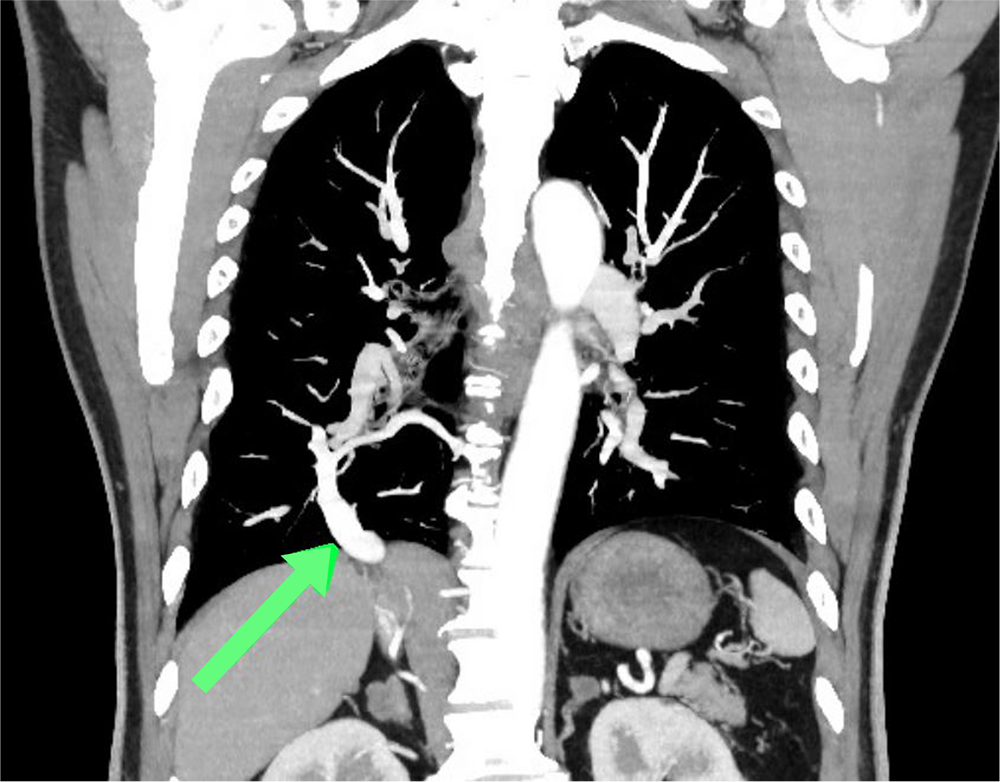

図2.造影CT(動脈相)冠状断MIP像

右肺下葉の肺静脈(矢印)は肝上部下大静脈に流入している。